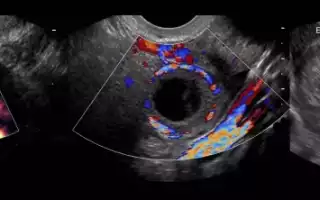

УЗИ-диагностика желтого тела

При нарушении регулярности менструаций, или задержке, специалисты настаивают на проведении ультразвукового исследования репродуктивных органов малого таза женщины. Такое обследование позволяет определить, присутствует ли желтое тело, состояние яичников и что послужило причиной этого нарушения.

Методом УЗИ определяется наличие и состояние железы, ее размеры и развитие, а так же выявляются возможные патологии и заболевания женских органов. Железа заметна на мониторе в виде неоднородной капсулы в области яичника разной величины на разных этапах менструального цикла.

Наличие нескольких желтых тел указывает на возможность многоплодной беременности. При ультразвуковой диагностике определяется овуляторная способность железы, полезная при планировании беременности, наличие кисты или бесплодия и возможности их устранения.